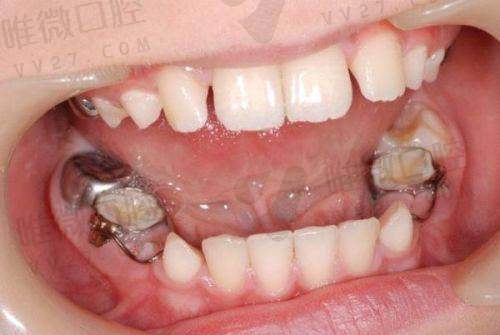

儿童早期干预矫正

:针对3-12岁儿童的口腔发育问题

- 乳牙早期矫正(MRC矫治器)